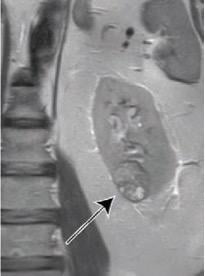

64-Year-Old Man With Clear Cell Likelihood Score (ccLS) 5 Renal Masses. Coronal T2-weighted single shot fast spin echo and coronal T1-weighted fat-saturated spoiled gradient echo acquired during corticomedullary phase—ccLS5 lesion outlined red for clarity.

Extracted from clinical reports, “the ccLS scores the likelihood that the small renal mass represents clear cell renal cell carcinoma, from 1 (very unlikely) to 5 (very likely),” explained corresponding author Ivan Pedrosa from the University of Texas Southwestern Medical Center at Dallas. “Small renal masses with lower ccLS may be considered for active surveillance, whereas small renal masses with higher ccLS may warrant earlier intervention.”